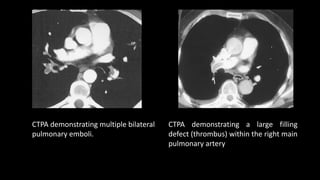

CTPA demonstrating multiple bilateral

pulmonary emboli.

CTPA demonstrating a large filling

defect (thrombus) within the right main

pulmonary artery